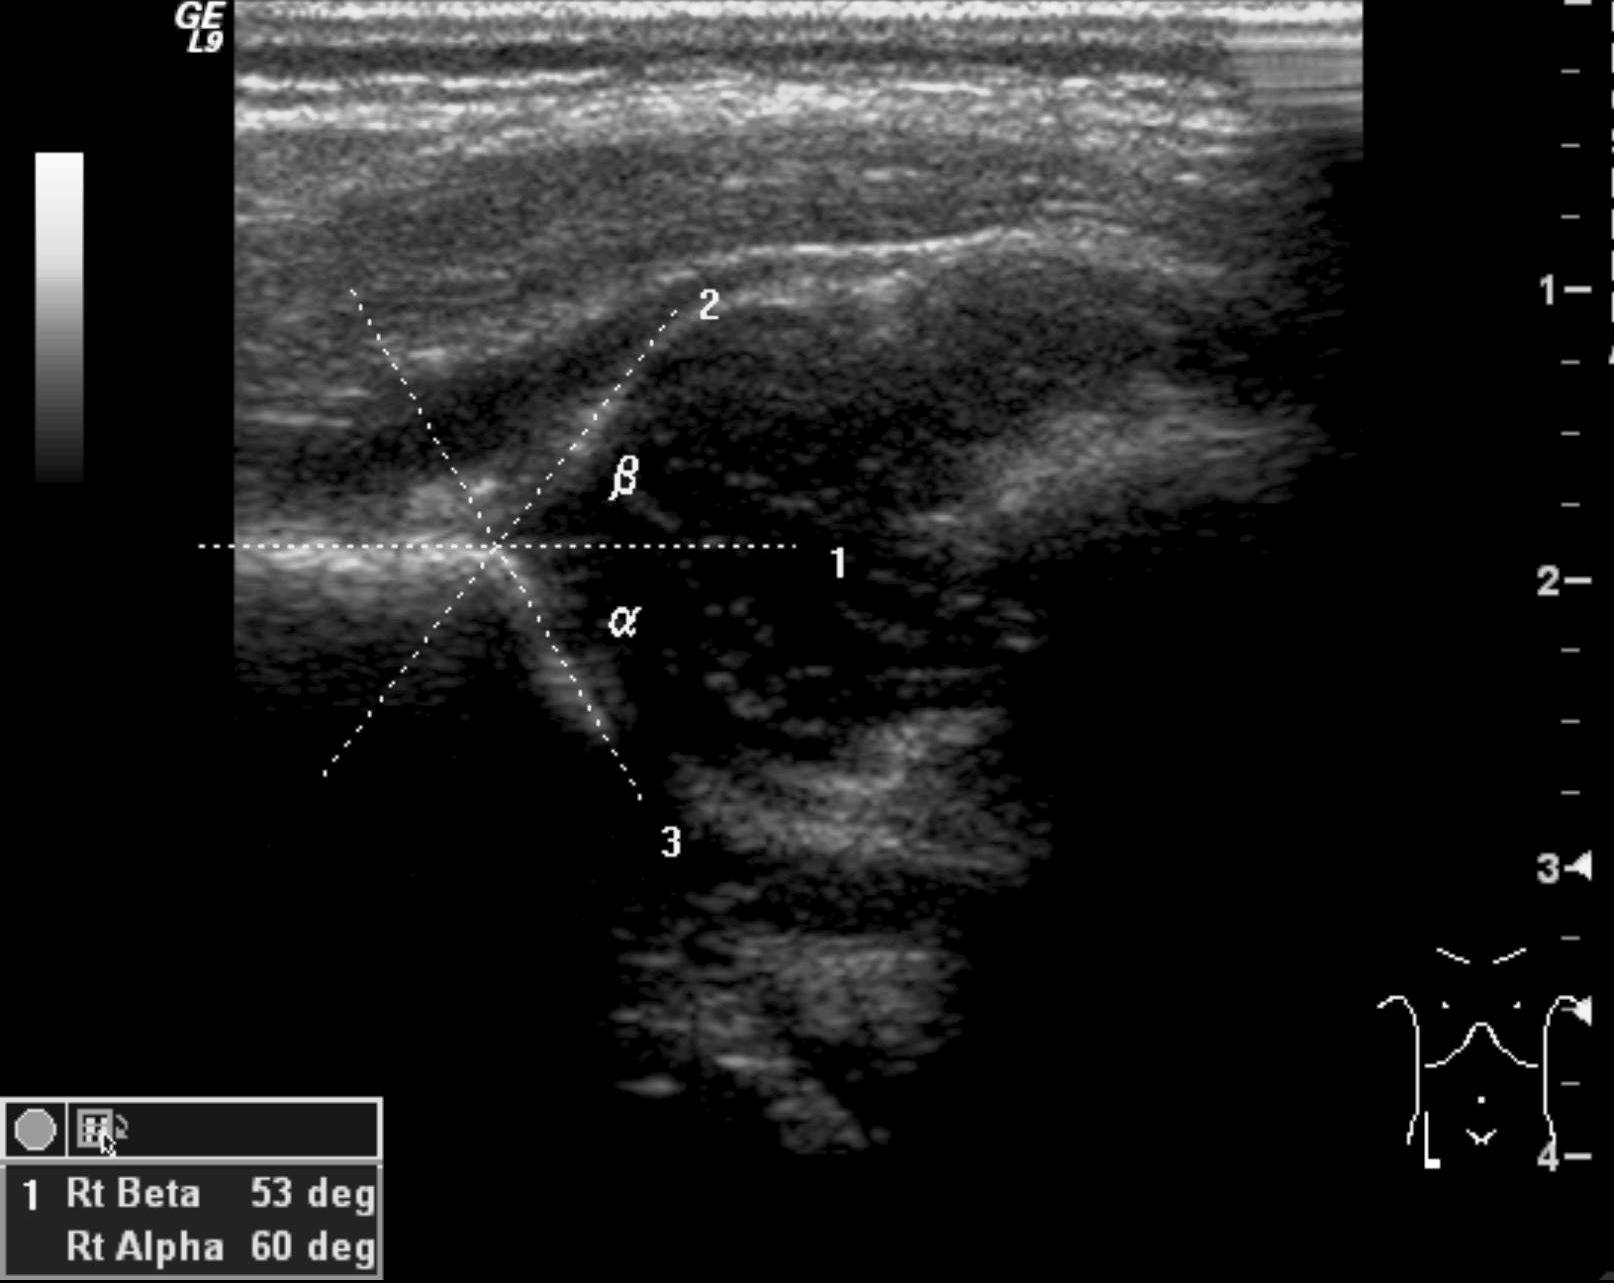

42. US examination. Normal newborn hip (arrow: hip bone.)

Hip dysplasia. Congenital hip dysplasia is a multifactorial disease that occurs more in girls (1:9) and causes the dislocation of the head of the femur. Acetabular rim development and configuration abnormalities, ligament looseness, muscle contracture, family history of hip dysplasia, or intrauterine breech position have all been mentioned as possible factors causing hip dysplasia. US examination is capable to diagnose infant hip dysplasia. It is indicated if the clinical examination raises suspicion or if risk factors (breech position, twin pregnancy, family history, oligohydramnion, deformed limb, neuromuscular disease) persist. US can be used as a screening tool. Due to the physiologic looseness of the ligaments before 4 weeks of age the hip is immature, therefore screening exam should take place after 4 weeks and can be performed until 4-6 months. X-ray exam: can only detect indirect signs of hip dysplasia until the appearance of the ossification centers of the femoral head.